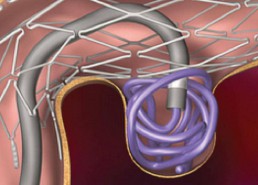

Two main treatment options exist: Endovascular coiling of aneurysms (where a catheter is inserted through arteries under x-ray guidance and tiny platinum based coils are placed inside the aneurysm), and open surgical clipping of aneurysms.

These devices include stents (wire tubes which line the vessel walls an allow treatment of aneurysms which would otherwise be unfavourable for coiling alone).

He uses a significant number of flow diverting stents, which are high mesh density stent used for treatment of very large or difficult aneurysms.